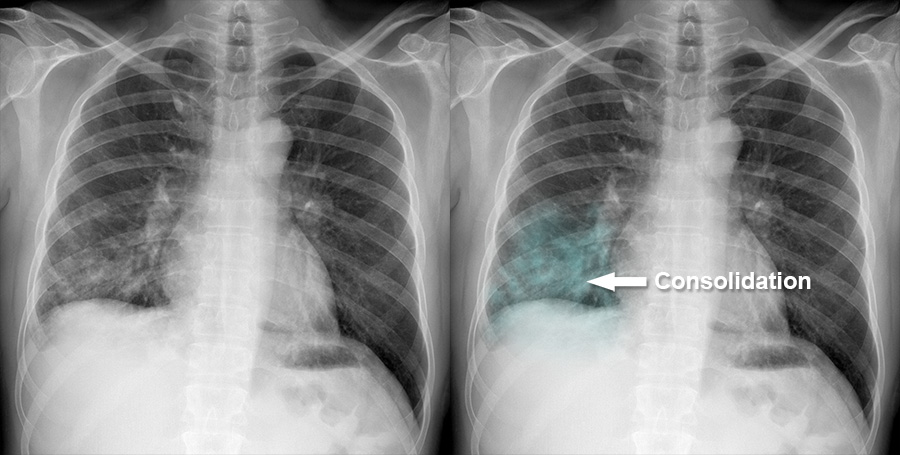

Chest X Ray Consolidation

Rt Lower Lobe Pneumonia